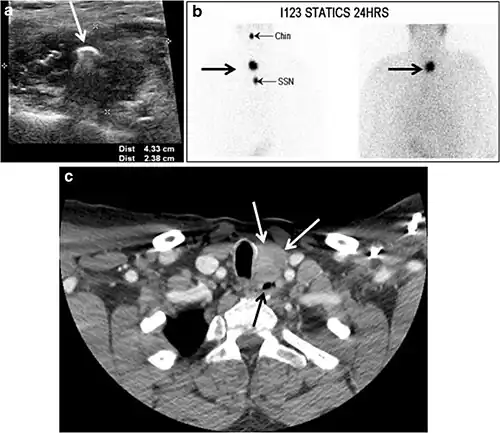

Fig. 8. A 48-year-old male patient post total thyroidectomy with PTC recurrence. a Transverse greyscale ultrasound of the neck demonstrates a left thyroid bed heterogeneous, predominantly hypoechoic irregular lesion with calcifications (white arrow). b A spot image of iodine 123 total body scan of the neck demonstrate a focus of abnormal radiotracer uptake at the left thyroid bed (Black arrows) between the annotated markers. c Enhanced axial CT scan of the neck demonstrates an enhancing large left thyroid bed mass (white arrow) with no calcifications. The lesion exerts a mass effect on the oesophagus (black arrow) and is inseparable from the trachea.[1]

-